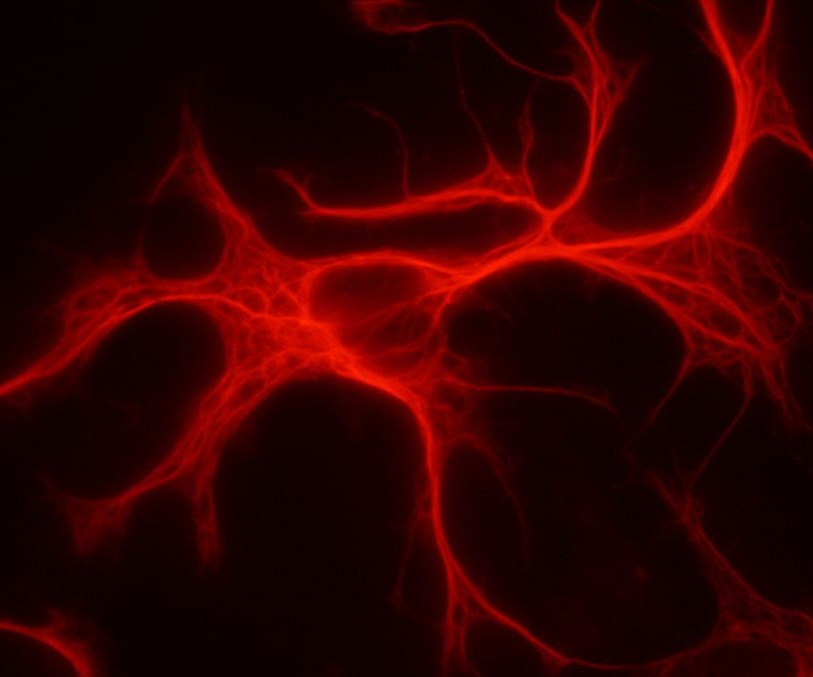

Astrocito. Imagen: Grzegorz Wicher. Fuente: Wikipedia.

En concreto se trata de los astrocitos, un tipo de células gliales con forma de estrella que se encuentran en la médula espinal y el cerebro, donde son las células más abundantes.

Los astrocitos tienen un elevado número de funciones clave para la realización de la actividad nerviosa, y se originan en las primeras etapas del desarrollo del sistema nervioso central. En los seres humanos, son más grandes, abundantes, diversos y complejos que en otras especies.

En concreto se trata de los astrocitos, un tipo de células gliales con forma de estrella que se encuentran en la médula espinal y el cerebro, donde son las células más abundantes.

Los astrocitos tienen un elevado número de funciones clave para la realización de la actividad nerviosa, y se originan en las primeras etapas del desarrollo del sistema nervioso central. En los seres humanos, son más grandes, abundantes, diversos y complejos que en otras especies.

Los astrocitos son vitales para el pensamiento consciente, ya que ayudan a fortalecer las conexiones entre neuronas o sinapsis. Sus extensiones en forma de zarcillo están implicadas en la coordinación de la transmisión de señales eléctricas.

Los astrocitos humanos son entre 10 y 20 veces el tamaño de los astrocitos de ratón y cuentan con 100 veces más extensiones. Esto significa que pueden coordinar todas las señales neuronales de un área mucho más hábilmente que los astrocitos de un ratón.

Los astrocitos son vitales para el pensamiento consciente, ya que ayudan a fortalecer las conexiones entre neuronas o sinapsis. Sus extensiones en forma de zarcillo están implicadas en la coordinación de la transmisión de señales eléctricas.

Los astrocitos humanos son entre 10 y 20 veces el tamaño de los astrocitos de ratón y cuentan con 100 veces más extensiones. Esto significa que pueden coordinar todas las señales neuronales de un área mucho más hábilmente que los astrocitos de un ratón.